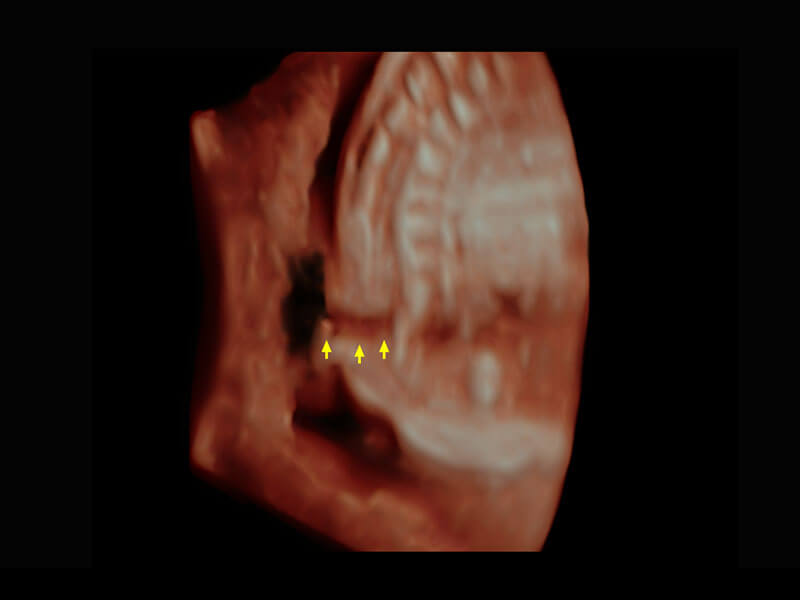

P60搭載一系列胎兒心臟成像技術(shù),實(shí)現(xiàn)精細(xì)的胎兒心臟評(píng)估。

右室雙出口

胎心容積成像